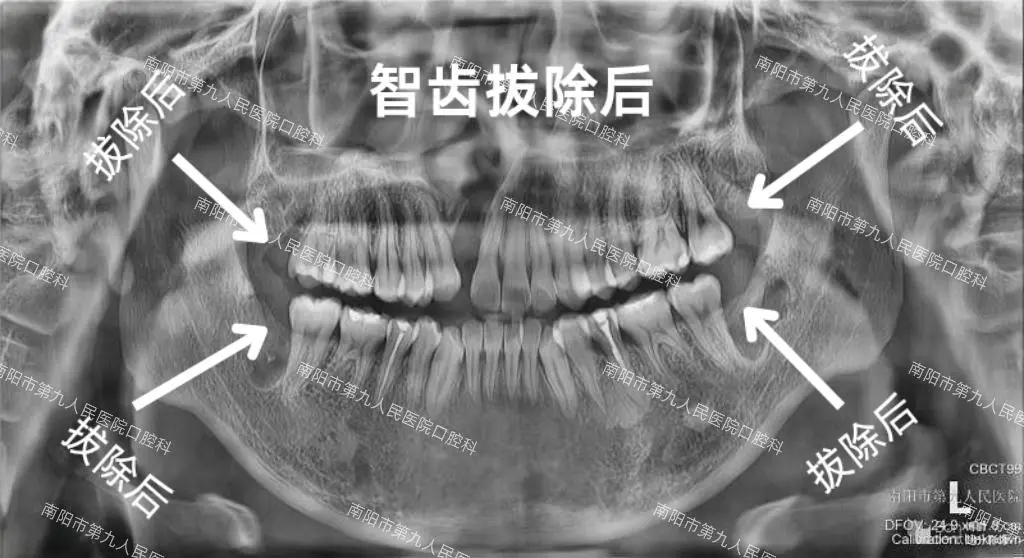

患者儿子智齿拔除前后X光对比图

患者朋友说:“这次孩子的体验,却完全颠覆了我对‘拔牙’的恐惧:李医生会一步步和孩子解释流程,安抚他的紧张情绪,连一向怕看牙的孩子事后都拉着我说‘医生叔叔好温柔’。整个过程是微创的,孩子说全程几乎没有痛感,拔完也没有明显的肿胀。更让我们安心的是,结束后李医生还特意叮嘱了术后护理的细节,比如怎么冰敷、吃什么食物更合适。”